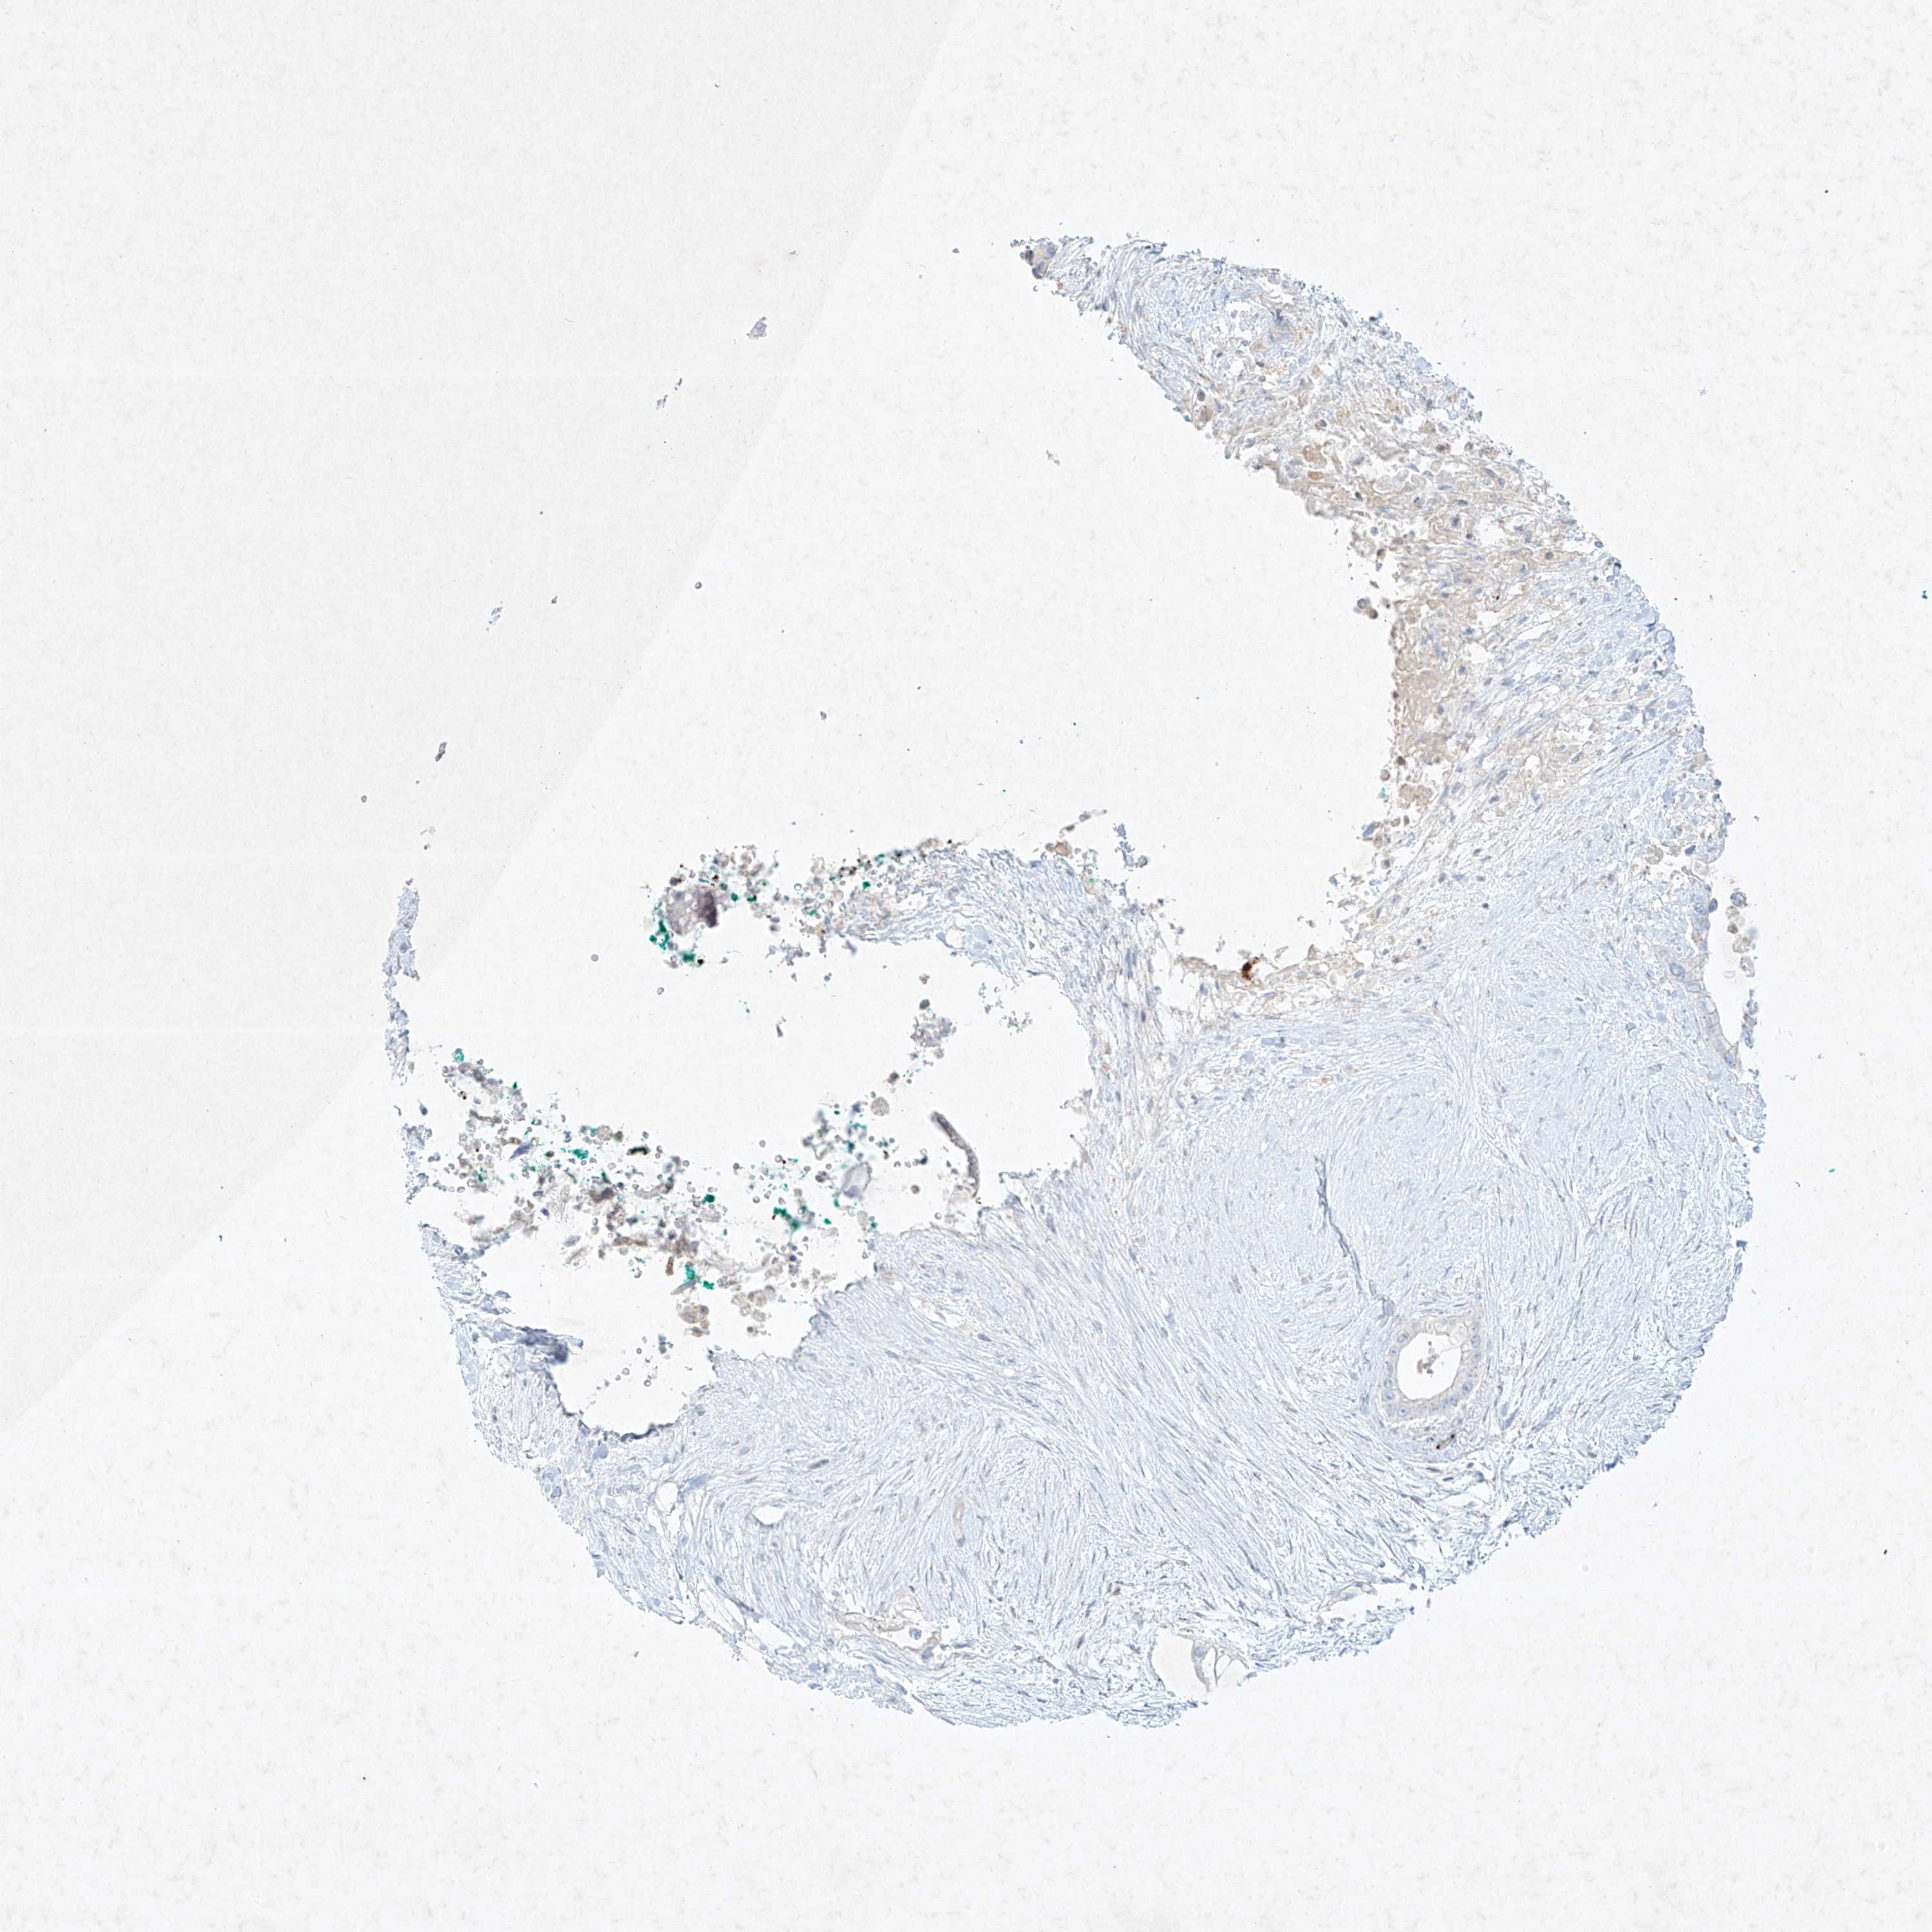

PANCREATIC CANCER - Protein expressioni

A mouse-over function shows sample information and annotation data. Click on an image to view it in a full screen mode. Samples can be filtered based on level of antibody staining by selecting one or several of the following categories: high, medium, low and not detected. The assay and annotation is described here.

Note that samples used for immunohistochemistry by the Human Protein Atlas do not correspond to samples in the TCGA dataset.

Antibody stainingi

Antibody staining in the annotated cell types in the current human tissue is reported as not detected, low, medium, or high, based on conventional immunohistochemistry profiling in selected tissues. This score is based on the combination of the staining intensity and fraction of stained cells.

Each image is clickable and will lead to virtual microscopy that enables deeper exploration of all samples and also displays staining intensity scores, fraction scores and subcellular localization as well as patient and tissue information for each sample.

Antibody HPA031838

Antibody HPA057341

Adenocarcinoma, NOS